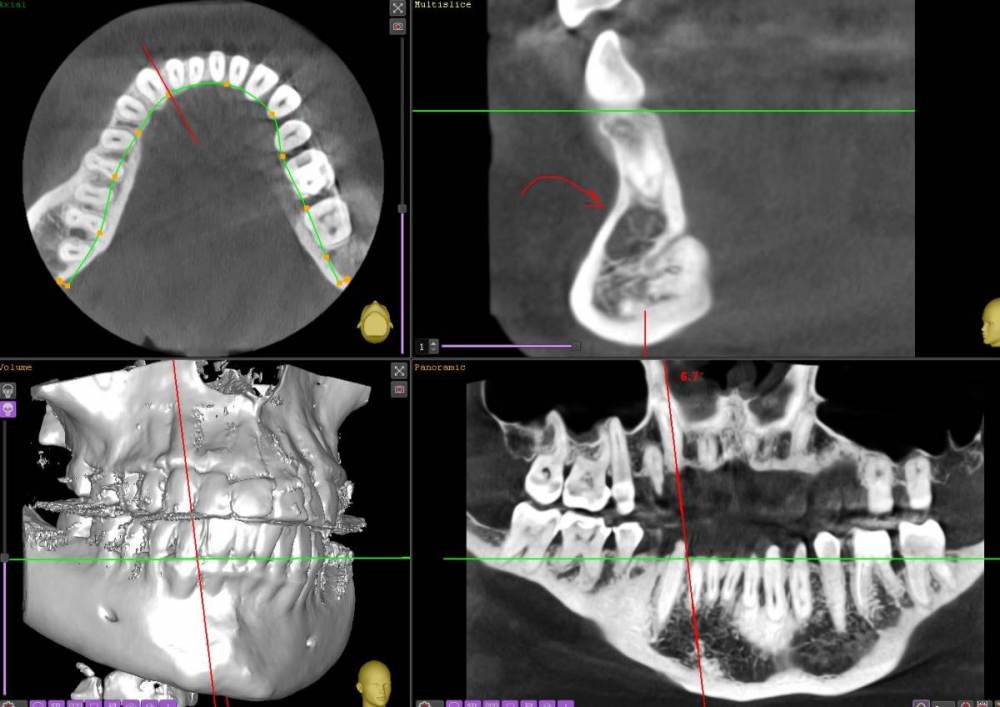

nevlvi Опубликовано 1 апреля, 2021 Поделиться Опубликовано 1 апреля, 2021 Добрый вечер, уважаемые коллеги. Увидел на КТ непонятные для меня структуры. Пока что только КТ, пациента еще не видел. Хотел бы уточнить что именно это может быть? Ссылка на комментарий

Astronaft Опубликовано 2 апреля, 2021 Поделиться Опубликовано 2 апреля, 2021 (изменено) Если будете вертеть КТ и такие очаги разрежения на нескольких витальных зубах то может быть цементная дисппазия. Главное сгоряча не пульпировать эти зубы. Цитата Периапикальная цементно-костная дисплазия (периапикальная цементная дисплазия, периапикальная фиброзная дисплазия, костная дисплазия, цементома) – это одиночное или множественное очаговое доброкачественное изменение костной ткани в зоне верхушки зубов, имеющих, как правило, витальную пульпу. Картинки Изменено 2 апреля, 2021 пользователем Astronaft Ссылка на комментарий